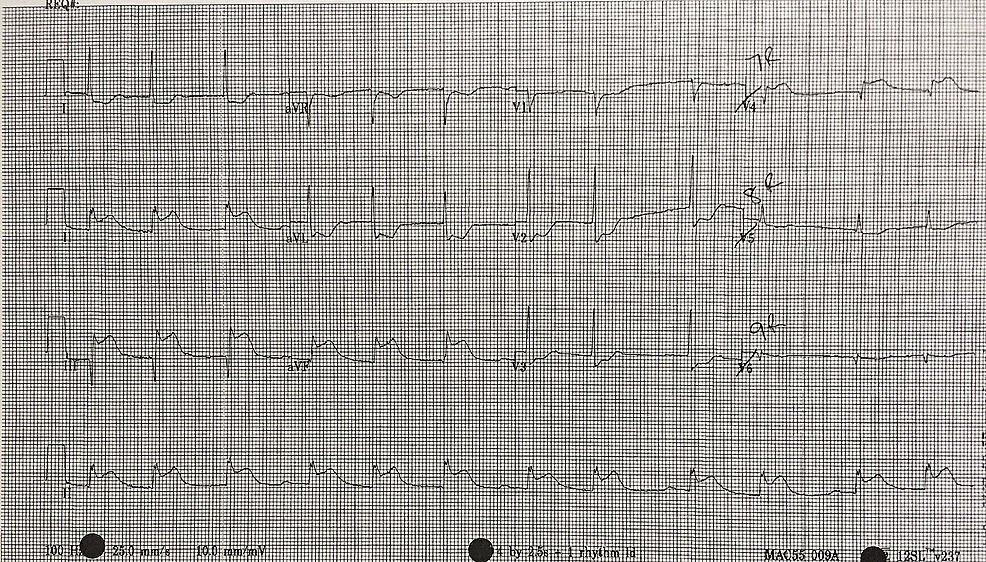

5)Localizzazione Inferiore Derivazioni interessate II, III, aVF Vaso interessato Arteria coronaria destra 6)Localizzazione Posteriore Derivazioni interessate R alta in V1V2 e sottoslivellamento di ST Vaso interessato Arteria coronaria destra 7)Localizzazione Ventricolare destra Derivazioni interessate V3R, V4R. Salvatore De Rosa, Carmen Spaccarotella, Cristina Basso, Maria Pia Calabrò, Antonio Curcio, Pasquale Perrone Filardi, Massimo Mancone, Giuseppe Mercuro, Saverio Muscoli, Savina Nodari, Roberto Pedrinelli, Gianfranco Sinagra, Ciro Indolfi, Società Italiana di Cardiologia and the CCU Academy investigators group, Reduction of hospitalizations for myocardial infarction in Italy in the COVID19. Inferior STEMI Above is an ECG in a patient having an acute inferior STEMI Note the ST elevations (tombstones) This is caused by total occlusion of the right coronary artery shown below.

Hvis EKG viser STelevationer er der tale om STEMI – ellers er der tale om NonSTEMI Nedenunder ses typisk EKG for STEMI ved anteriort og inferiort infarkt Der ses ofte ikke STEMI i posteriore infarkter Anteriore infarkter skyldes ofte okklusion af LAD, mens inferiore infarkter skyldes okklusion af RCA (nogle gange RX). Definition and assessment of STEMI is described in Acute Coronary Syndromes;. STElevation Myocardial Infarction (STEMI) is a very serious type of heart attack during which one of the heart’s major arteries (one of the arteries that supplies oxygen and nutrientrich blood to the heart muscle) is blocked STsegment elevation is an abnormality detected on the 12lead ECG Electrocardiogram with STsegments elevated.

Il principale punto di forza dello stent dissolvente è che viene assorbito dall’organismo in 3 anni È stato dimostrato non inferiore allo stent Xience a slim4vit uomo rilascio di everolimus negli studi ABSORB, sebbene con una tendenza preoccupante di più trombosi da scaffold (1,54% contro 0,74% per Xience). Si avranno così un infarto anteriore, laterale, inferiore, posteriore 087 0 In alcuni casi si avrà anche un infarto subendocardico 254, oppure microinfarti diffusi 255 Questa è una situazione molto frequente in casi di malattia coronarica che si sia protratta per molto tempo. Inferior STEMI can result from occlusion of all three coronary arteries The vast majority (~80%) of inferior STEMIs are due to occlusion of the dominant right coronary artery (RCA) Less commonly (around 18% of the time), the culprit vessel is a dominant left circumflex artery (LCx).

Inferiore Güter {pl} billige Ersatzgüter {pl} Sättigungsgüter {pl}econ inferior goods {pl} minderwertige Ware {f}comm inferior grade minderwertigere Sorte {f} inferior horn Cornu inferius, Cornu temporale lateral ventricle;. Supplementary Appendix This appendix has been provided by the authors to give readers additional information about their work Supplement to Tardif JC, Kouz S, Waters DD, et al Efficacy and. ECG in STEMI • Definition of STEMI –New ST elevation at the J point in two contiguous leads of >01 mV in all leads other than leads V2V3 –For leads V2V3 the following cut points apply ≥02 mV in men ≥40 years, ≥025 mV in men.